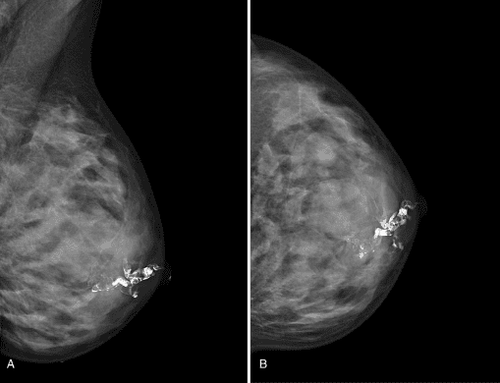

Chất cản quang được tiêm vào ống dẫn sữa vùng núm nhằm hiện hình các ống dẫn sữa trên phim chụp quang tuyến vú. Trên phim, chất cản quang trong các ống dẫn sữa có màu trắng. Nếu có hình ảnh khuyết trong lòng ống dẫn sữa (tương ứng với vùng màu đen), điều đó có nghĩa là có tổn thương choán chỗ trong ống dẫn sữa.

Các tổn thương này có thể là bướu lành hoặc bướu ác tính. Với kỹ thuật chụp ống tuyến vú không những tìm thấy bất thường trong ống dẫn sữa mà còn định vị bất thường, hướng dẫn cho bác sĩ phẫu thuật. Trong một số trường hợp, không có tổn thương choán chỗ, mà chỉ có hình ảnh giãn các ống dẫn sữa, đây có thể là một dấu hiệu của bệnh lý thay đổi sợi bọc vú, đây là bệnh lý có thể gây chảy máu, nhưng nói chung không đáng lo ngại.